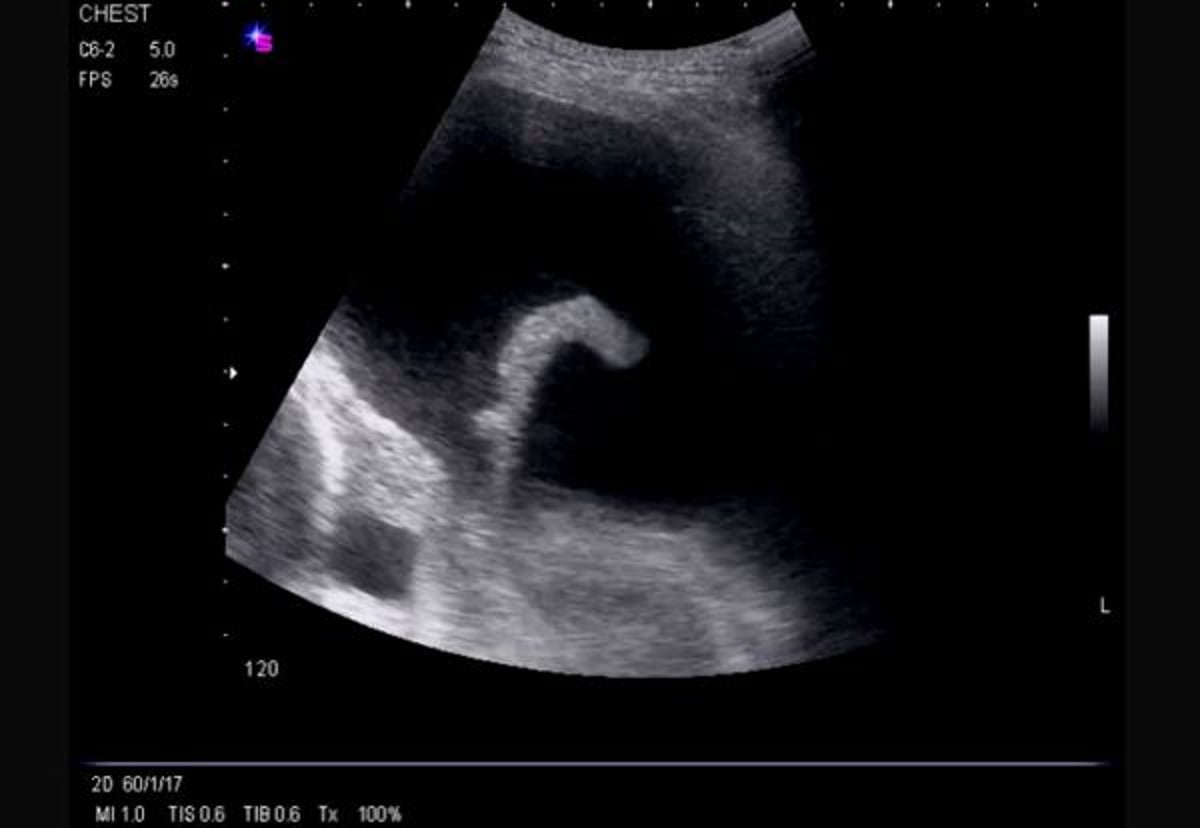

Ecografia toracica di profilo (sinistra)

Questa ecografia mostra un ampio versamento libero sul lato sinistro che causa un'atelettasia compressiva del lobo inferiore sinistro e rivela il ventricolo sinistro.

Image courtesy of Najib M. Rahman, BMBCh MA (oxon) DPhil.